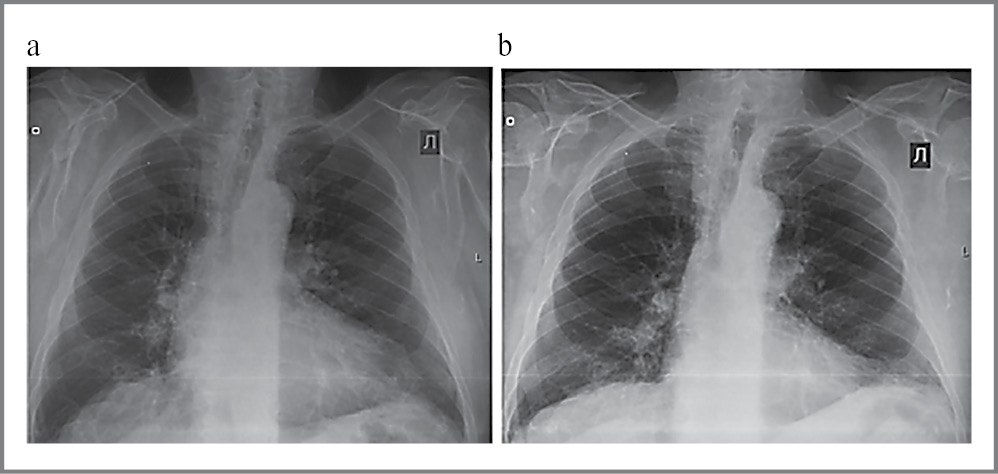

Интубация выполнена с 1-й попытки, пациенту успешно имплантирован биологический протез Acurate Neo размера L с сохранением минимальной остаточной регургитации. Послеоперационный период протекал без осложнений. По данным контрольного обследования запирательная функция протеза удовлетворительная, парапротезная регургитация минимальна. Отмечаются нормализация легочной гемодинамики, прирост фракции выброса (ФВ) ЛЖ, по данным рентгенографии легких – нормализация КТИ (рис. 10).

Рис. 10. Рентгенография органов грудной клетки, слева до операции, справа – спустя неделю после. Отмечаются отсутствие нарушений легочной гемодинамики, уменьшение размеров сердца.

Fig. 10. Chest X-ray. On the left: before the surgery; on the right: a week after the surgery. A decrease in the size of the heart and no pulmonary hemodynamics disorders were observed.

Динамика основных клинико-инструментальных показателей представлена в табл. 4.

КТИ, % | 60 | 50 |